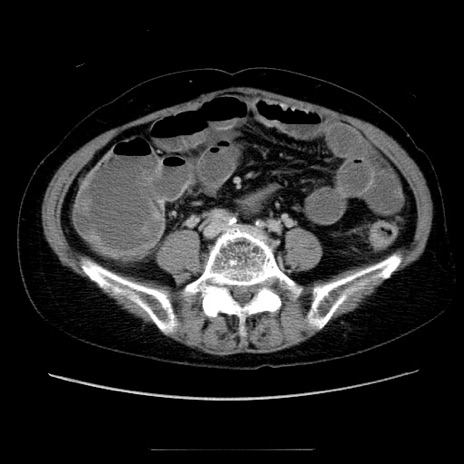

症例5(横断像)

【症例】70歳代女性

【主訴】お腹が張る

【現病歴】1週間くらい前から腹部膨満の自覚あり。昨日夜から増悪したため、本日救急外来受診。

【身体所見】意識清明、BT 36.5℃、BP 165/106mmHg、HR 80bpm、SpO2 98%、腹部:膨満、軟、自発痛・圧痛なし、触診にて不快感あり、腸蠕動音:減弱

【データ】WBC 12600、CRP 1.04